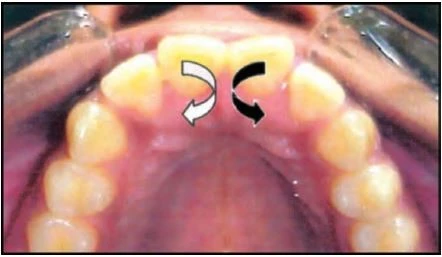

1.7 RĂNG XOAY

Đây là tình trạng những răng di chuyển xung quanh trục dọc của nó. Có hai kiểu xoay răng:

Gần trong hoặc xa ngoài

Mặt gần của răng nghiêng vào trong, hay nói cách khác mặt xa của thân răng nằm về phía ngoài so với mặt gần.

Xa trong hoặc gần ngoài

Mặt xa của răng nghiêng vào trong, hay nói cách khác mặt gần của thân răng nằm về phía ngoài so với mặt xa của nó.